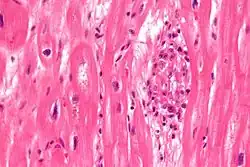

Microscopically, Aschoff bodies are areas of inflammation of the connective tissue of the heart, or focal interstitial inflammation. Fully developed Aschoff bodies are granulomatous structures consisting of fibrinoid change, lymphocytic infiltration, occasional plasma cells, and characteristically abnormal macrophages surrounding necrotic centres. Some of these macrophages may fuse to form multinucleated giant cells. Others may become Anitschkow cells or "caterpillar cells," so named because of the appearance of their chromatin.

They are pathognomic foci of fibrinoid necrosis found in many sites, most often the myocardium. Initially they are surrounded by lymphocytes, macrophages, and a few plasma cells, but they are slowly replaced by a fibrous scar. Aschoff bodies are found in all the three layers of the heart, least chance in the pericardium.

The Aschoff nodules are foci of T lymphocytes, occasional plasma cells, and activated macrophages (Anitschkow cells) pathognomonic of rheumatic fever. These macrophages have abundant cytoplasm and central round nuclei in which chromatin condenses into a central, slender, wavy ribbon, the reason why they are sometimes called "caterpillar cells". They are especially found in the vicinity of small blood vessels in the myocardium and endocardium and occasionally in the pericardium, and also the adventitia of the proximal part of the aorta. Lesions similar to the Aschoff nodules may also be found in extra-cardiac tissues.